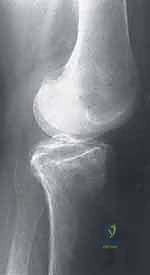

2. التصوير بالأشعة السينية (X-rays)

هي الخطوة التصويرية الأولى والأساسية. يطلب الدكتور هطيف صوراً بوضعيات محددة (أمامية خلفية، جانبية، وضعية النفق Notch view، ووضعية شروق الشمس Skyline view) أثناء الوقوف (تحميل الوزن). تساعد الأشعة السينية في رؤية العيوب العظمية، وتحديد حجم الآفة، واكتشاف أي أجسام حرة (Loose bodies) متكلسة داخل المفصل.